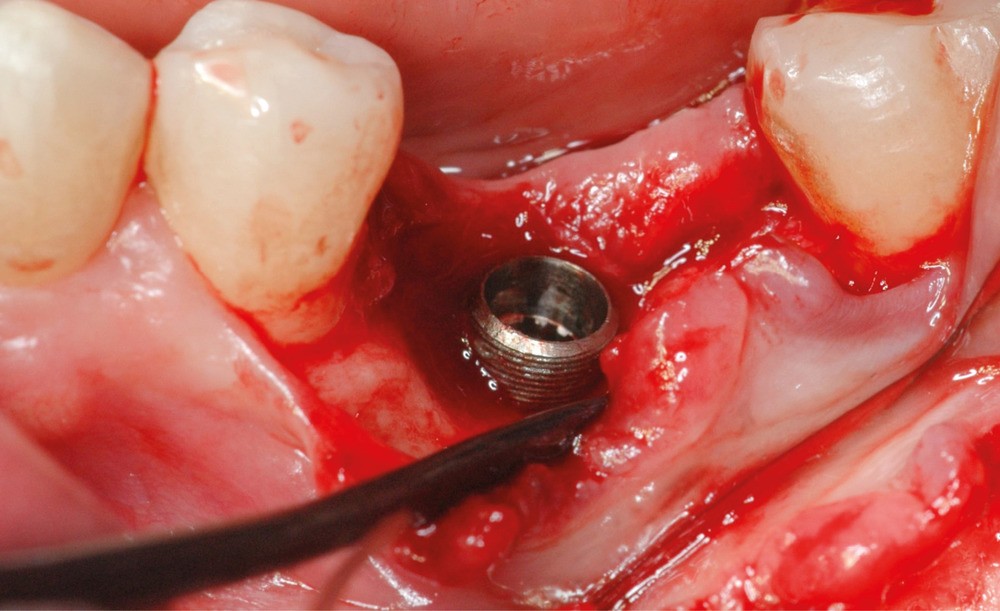

- Avulsion de la 36 et régénération osseuse guidée (ROG) réalisée en 2017 suite à une fracture de la dent et une infection

- Un implant posé en 2018 après la fin du traitement orthodontique

- Péri-implantite diagnostiquée en 2021

Chez ce patient, le traitement de la péri-implantite a comporté une chirurgie associant décontamination électrolytique de la surface implantaire, régénération osseuse guidée et enfouissement de l’implant. Le résultat à 2 ans est très moyen au vu du pourcentage de régénération osseuse obtenu. Comment peut-on prévoir un tel résultat alors que l’on a suivi les recommandations à la lettre, que l’on a utilisé les dernières technologies de décontamination, que l’on y a mis tous les moyens, que le patient est en bonne santé générale et qu’il vient en plus régulièrement aux séances de thérapeutique de soutien ? Le succès du traitement des péri-implantites n’est pas simple à obtenir, surtout quand un élément clé est compromis… la maintenance personnelle ! En effet le succès n’est possible que si le contrôle de plaque quotidien est optimal et, ici, ça n’était pas le cas. Le patient se brossait certes les dents, mais ne passait pas quotidiennement les brossettes, ce qui…